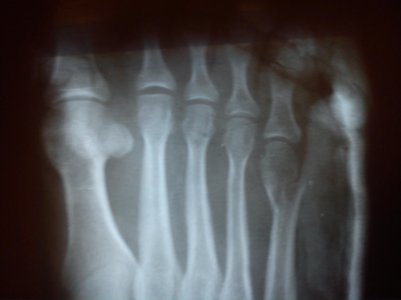

Рентген11.05